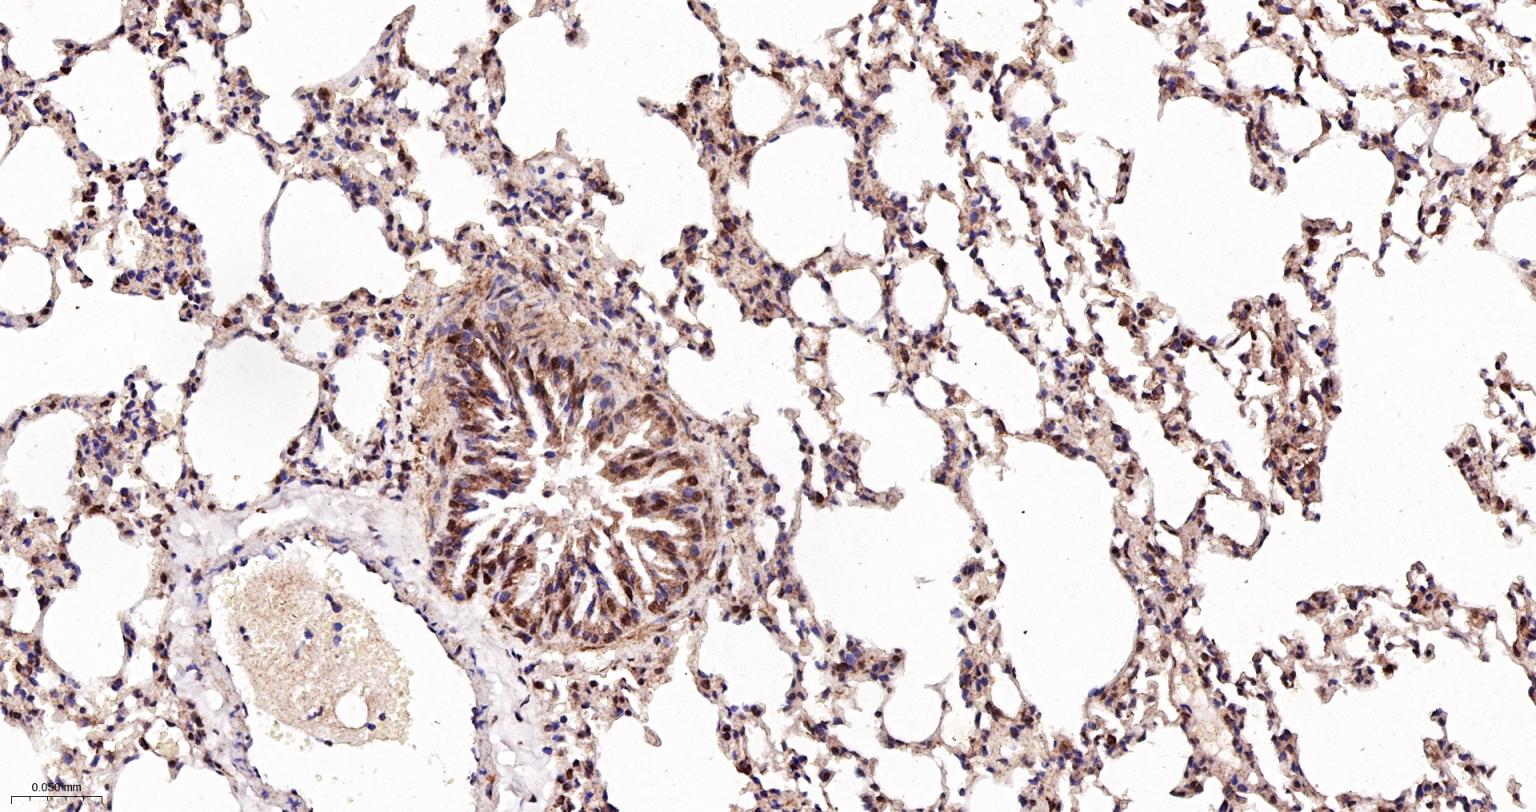

Paraformaldehyde-fixed, paraffin embedded Human Lung; Antigen retrieval by boiling in sodium citrate buffer (pH6.0) for 15 min; The section was incubated with MAD2L2 Monoclonal Antibody, Unconjugated (bsm-61670R) at 1:200 overnight at 4°C, followed by conjugation to the bs-0295G-HRP and DAB (C-0010) staining.